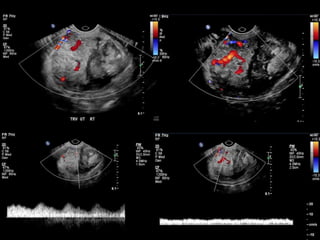

HISTORY

• 65 yo female

• Presents from OSH with worsening ‘left

breast swelling’ for 8-9 months

• New 1 month history of ‘change in left

nipple’

Current Bilateral Mammogram

RCC      LCC             RMLO       LMLO

Current and Comparison Left Breast MGs

4 YRS PRIOR               CURRENT              4 YRS PRIOR

US retroareolar region

US Left upper outer breast

• What are the findings?

• What would you do next?

• What is your differential diagnosis?

• What are your recommendations?